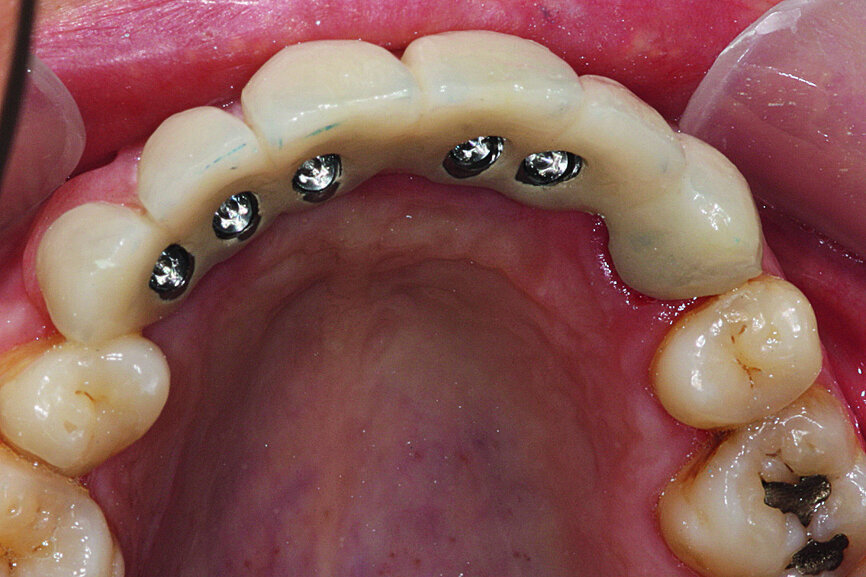

Fig. 28: The prosthesis was attached with screws and the necessary occlusal verification was conducted.

Fig. 29: The prosthesis was attached with screws and the necessary occlusal verification was conducted.

After four months, the implants were loaded using an apically positioned flap. The healing abutments were placed and the flap sutured around them (Fig. 17). Radiographic analysis and especially a percussion test showed the implants’ perfect osseointegration. After 15 days of gingival healing around the abutments, they were removed and the impression copings were placed and secured with a self-curing resin (Fig. 18). Impressions were taken and the healing screws were reinserted (Figs. 19 & 20).